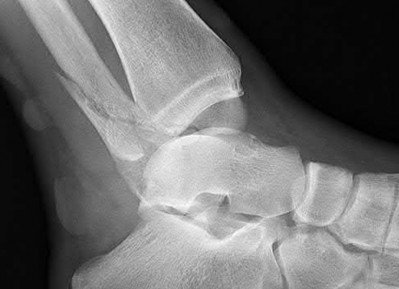

Question 2:

A 28-year-old male sustains a severe hyper-dorsiflexion injury to his ankle in a motor vehicle accident, resulting in a Hawkins Type III talar neck fracture. Which of the following arteries provides the predominant blood supply to the body of the talus, placing it at significant risk for avascular necrosis in this injury?

Correct Answer: Artery of the tarsal canal

Explanation:

The artery of the tarsal canal, which is a branch of the posterior tibial artery, provides the dominant blood supply to the talar body. In a Hawkins Type III fracture (talar neck fracture with subtalar and tibiotalar dislocation), the blood supply from the artery of the tarsal canal, the artery of the sinus tarsi, and capsular vessels are disrupted, leading to an avascular necrosis (AVN) rate approaching 100%.